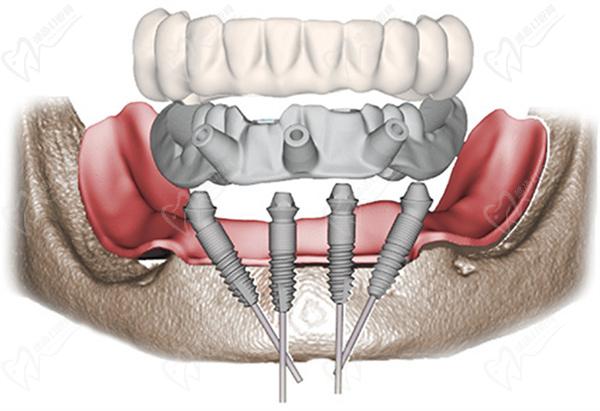

一、all on 4种植牙+马龙桥种植图解

All-on-4种植牙

【All-on-4种植技术】

All-on-4是一种即刻种植牙技术,它指的是在全口牙齿缺失的情况下,通过在上下颌骨的4个位置植入种植体,以支持全口义齿或部分义齿的修复。